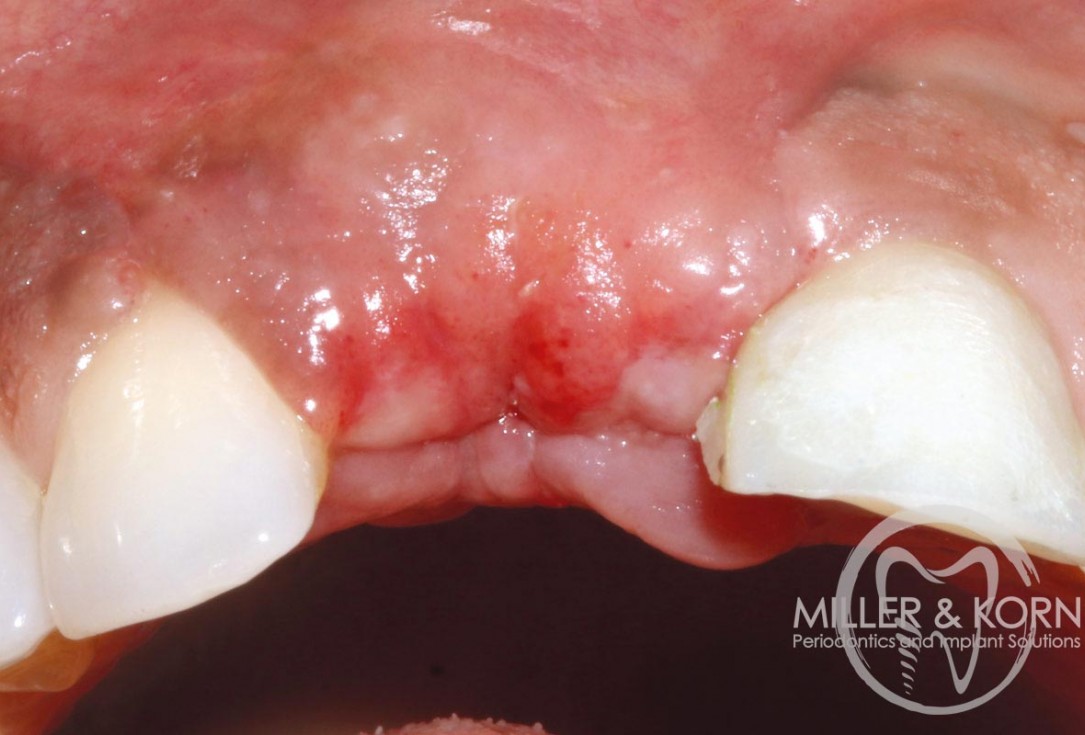

1/22 - 60-year-old female patient presented with a chronic infection on tooth #11. Since she has a high lip line matching the gingival margins of the adjacent central incisor and creating a root eminence is extremely important. For these reasons, the treatment of choice was an allograft bone ring enabling immediate placement of the dental implant with simultaneous regeneration of her ridge.Immediate implant placement and regeneration of ridge using an allograft bone ring and Jason® membrane - Drs. Miller and Korn

60-year-old female patient presented with a chronic infection on tooth #11.

Since she has a high lip line matching the gingival margins of the adjacent central incisor and creating a root eminence is extremely important. For these reasons, the treatment of choice was an allograft bone ring enabling immediate placement of the dental implant with simultaneous regeneration of her ridge.